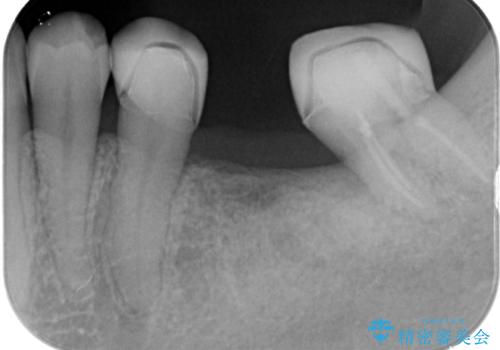

- 左下のブリッジの適合が悪く、虫歯になっていました。

左下6を抜いてからブリッジを入れるまでに放置してしまったために、左下7が前に倒れたこと、左下8も後ろから押す向きに生えていたこともあり、左下7がかぶせものを入れづらい状態になっていたためと考えられました。

また左下7は倒れていたため、清掃性が悪く近心のポケットは7mmありました。